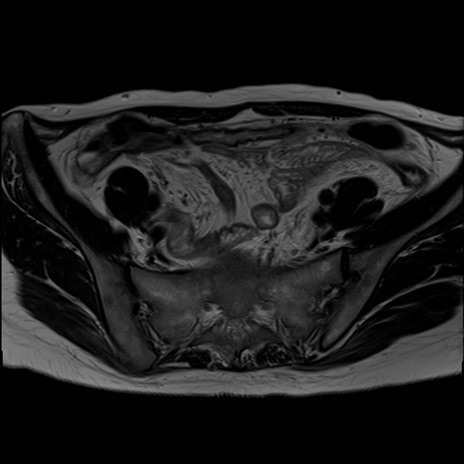

症例39 T2WI(横断像)

MRI(4日後)